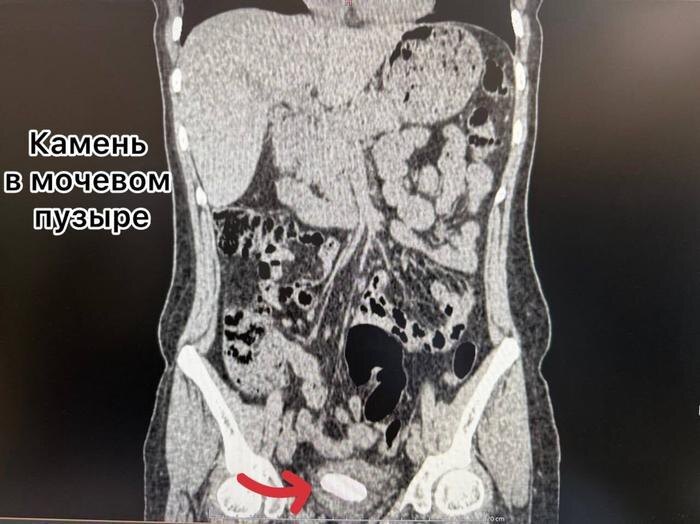

Выяснилось, что мочеточниковый стент был установлен женщине два года назад, но по какой-то причине его своевременно не извлекли. В результате инородный предмет затвердел, а в почке и мочевом пузыре пациентки образовались конкременты. Медики провели сложную многоэтапную операцию, в ходе которой одновременно удалили как сам стент, так и образовавшиеся в органах камни.

"Через один минимальный прокол в пояснице (метод перкутанной нефролитотрипсии) с помощью ультразвука был разрушен и удалён почечный камень. Одновременно, через естественные пути, современным лазером Urolase+ Premium был раздроблен и извлечен камень из мочевого пузыря и стент. Операция проводилась с применением эндоскопического оборудования и под рентген-контролем, что гарантировало высочайшую точность", - говорится в сообщении "Тысячекоечной больницы".